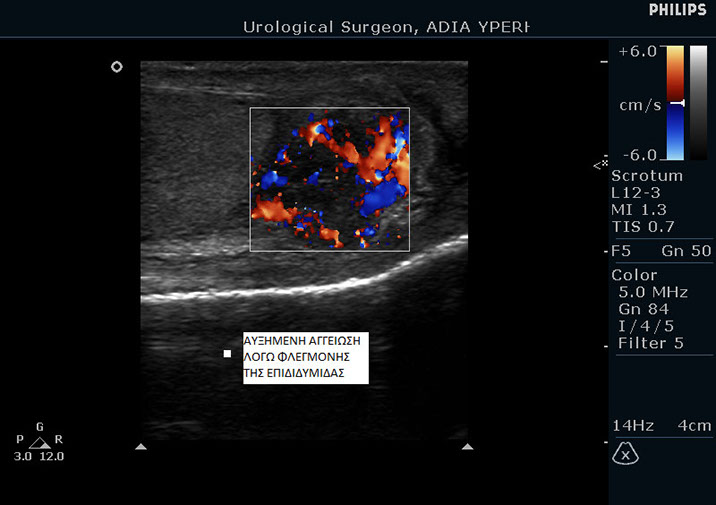

Επιδιδυμίτιδα του όρχι

Ως επιδιδυμίτιδα ορίζεται η φλεγμονή της επιδιδυμίδας σε κάποιον από τους δύο όρχεις. Επιδιδυμίτιδα ονομάζονται τα σωληνάκια που ξεκινάνε από τους όρχεις και μεταφέρουν το σπέρμα στην οπίσθια ουρήθρα.

Η διάγνωση γίνεται εύκολα από τον ουρολόγο με τη βοήθεια υπερήχων και της κλινικής εξέτασης.